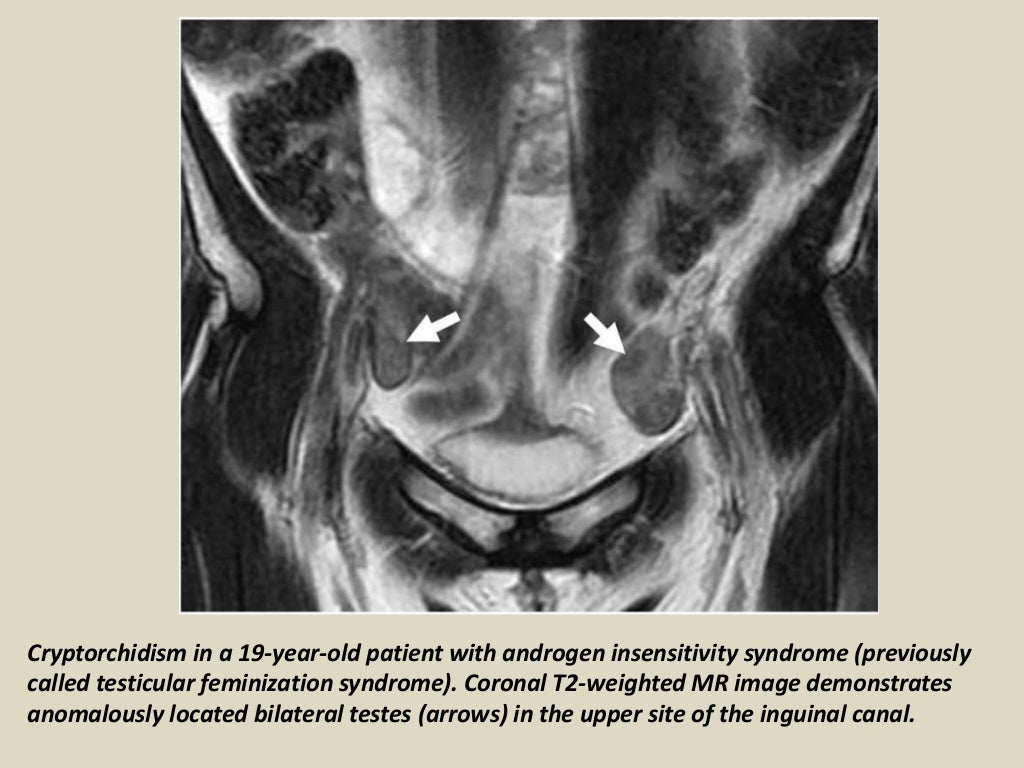

Undescended Testes MRI Sumer's Radiology Blog

Undescended Testes MRI Sumer's Radiology Blog What Is Undescended Testes In Tagalog The male reproductive system is composed of two main parts. This is a condition seen in. Most people have never heard of undescended testes, also called cryptorchidism. Undescended testes is when one or both of the male testes have not passed down (descended) into the scrotal sac. And 10% of the time, it’s bilateral or affecting both testes. Instead, it’s. What Is Undescended Testes In Tagalog.